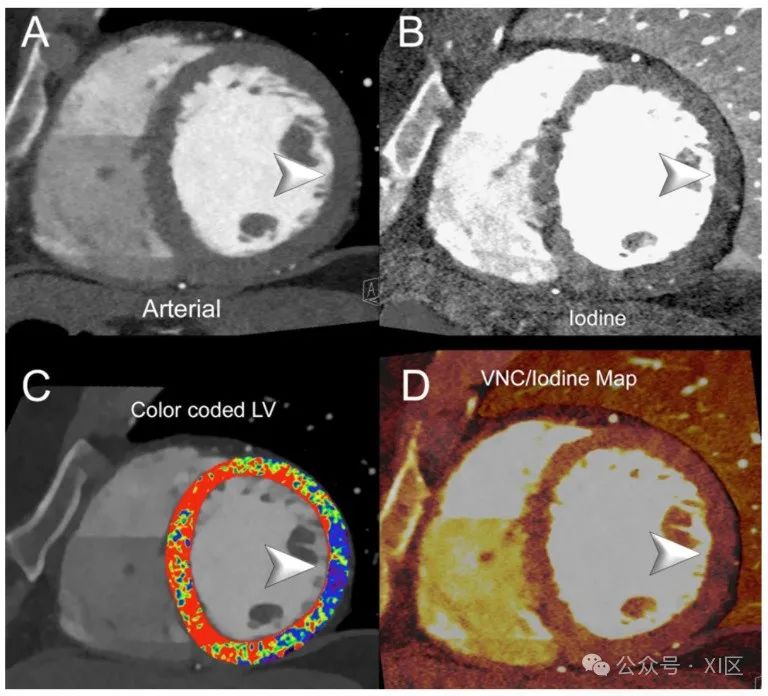

图3和图4展示了左心室缺血的PCCT示例。

图4 心脏/冠状动脉能谱PCCT示例,显示慢性左心室缺血。图中展示了一位接受心脏CT评估冠状动脉疾病的患者,在回顾性休息时表现出冠状动脉周围(LV侧壁)的延迟灌注。A显示左心室(LV)中基底短轴视图,为动脉/血管造影相位;B显示相同投影的碘分布;C显示具有色彩编码LV图的标准图像;D显示与虚拟平扫/碘叠加映射的相同投影。箭头在每个图中指示LV侧壁的明显灌注延迟(早期)。延迟相位采用了能谱采集和40 keV重建。扫描使用商用全身双源PCCT扫描仪(NAEOTOM Alpha,Siemens Healthineers)进行,层厚为0.2/0.4mm,重建间隔为0.1/0.2mm,FOV 140–160mm,源轴向重建的分辨率矩阵为512 × 512/1024 × 1024,使用Bv48-60卷积核和最大强度的量子迭代重建(QIR 4);扫描采用回顾性心电门控和管电流调制。显示的空间分辨率为0.1/0.20mm。一项模体研究显示,PCCT在碘图的碘定量和虚拟单色成像的CT值生成方面具有良好的准确性。